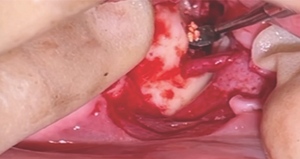

A unilateral sagittal split osteotomy was performed using piezosurgery to protect the nerve. The alveolar nerve, extending from the apical region of the left first and second molars to the mental foramen, was uncovered, and a meticulous dissection was performed to release it from the canal. Notably, rigid paste debris was observed in proximity to and within the nerve canal. The nerve exhibited signs of swelling and was surrounded by granulation tissue (Figures 4 and 5).